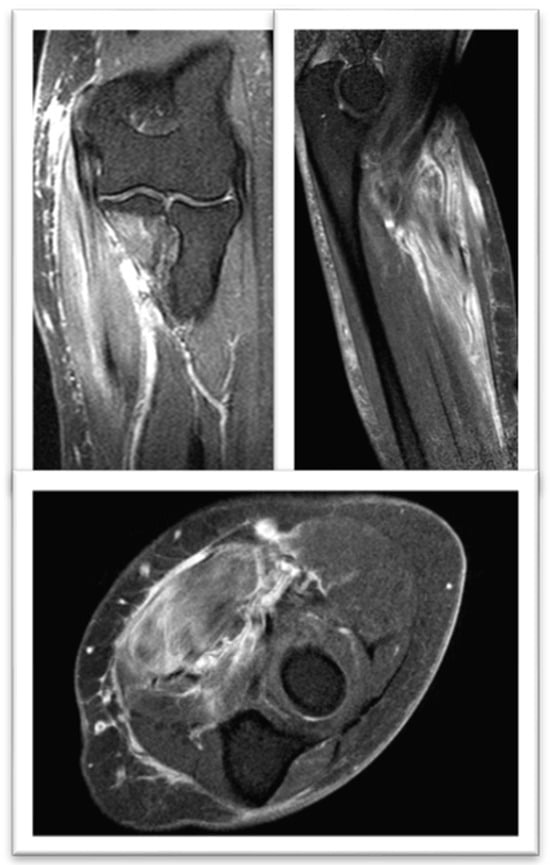

- Pinal-Fernandez, I.; Casal-Dominguez, M.; Carrino, J.A.; Lahouti, A.H.; Basharat, P.; Albayda, J.; Paik, J.J.; Ahlawat, S.; Danoff, S.K.; Lloyd, T.E.; et al. Thigh muscle MRI in immune-mediated necrotising myopathy: Extensive oedema, early muscle damage and role of anti-SRP autoantibodies as a marker of severity. Ann. Rheum. Dis. 2017, 76, 681–687. [Google Scholar] [CrossRef]